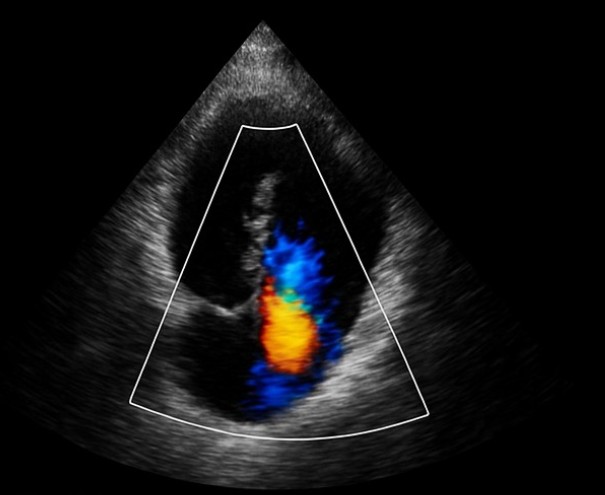

Gli ecotomografi più avanzati, che dispongono di soluzioni AI-based, offrono immagini bidimensionali di qualità eccellente, la possibilità di ricostruire tridimensionalmente la geometria cardiaca e acquisire varie misurazioni in tempi ridotti (volume ventricolare telediastolico e telesistolico, frazione di eiezione, massa del miocardio e volumi atriali massimi e minimi) e l’elaborazione automatica real time del documento di referto.

È stato condotto uno studio pilota finalizzato a valutare l’impatto di un test ecocardiografico di screening rapido (“Rapid Echocardiographic Screening Test”, REST): sono stati coinvolti, durante visita anestesiologica preoperatoria ambulatoriale, 229 pazienti candidati ad intervento elettivo di chirurgia non cardiaca, divisi in 2 gruppi: 53 con REST AI-oriented e 176 con REST normale. L’esame è stato condotto dallo stesso medico cronometrando il tempo tra il contatto e lo stacco della sonda ecografica dalla cute del paziente e valutando la qualità delle immagini ottenute. Oltre a fornire evidenza di anomalie non note in precedenza, che hanno richiesto sospensione dell’intervento previsto o ulteriori accertamenti cardiologici, il tempo medio di esecuzione è risultato inferiore a 7 minuti con REST normale mentre in caso di REST basato su AI-oriented non supera i 5 minuti.

Considerato che un’ecocardiografia tradizionale richiede in media 30 minuti, il REST garantisce un numero maggiore di prestazioni grazie ai tempi di esecuzione inferiori.